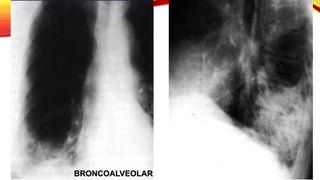

CARCINOMA BRONCOALVEOLAR

Subclasificacion del

adenocarcinoma

Se presenta con mayor

frecuencia en no fumadores

Lesión preinvasiva

Adenocarcinoma in situ

Adenocarcinoma invasivo

• Carcinoma bronquioalveolar presenta broncograma

aéreo y puede presentar cavitación

BRONCOALVEOLAR

Masa pulmonar en lóbulo inferior izquierdo con

múltiples imágenes nodulares bilaterales de

predominio en campos inferiores